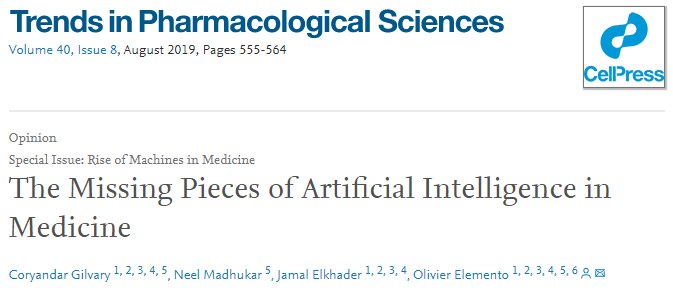

1.从实验室到临床的AI应用

近年来,人工智能技术在医疗保健研究中的使用急剧增加。产生和存储前所未有的大型数据集以及扩大计算规模的能力使AI蓬勃发展。大数据革命最大程度地增强了AI的子领域机器学习(ML),其中学习是通过暴露于预先存在的大型数据集来驱动的。这些发展共同为AI创造了新颖而令人兴奋的机会,可以在多个阶段积极影响医学领域。

AI最直接转变的医疗保健子领域是在皮肤病学、放射学或病理学等领域中基于图像的诊断方法。在一项开创性研究中,Esteva等人利用Google Inception卷积神经网络(CNN)架构从皮肤病变图像中对非黑色素瘤和黑色素瘤皮肤癌进行分类,并获得了与专家同等的结果。在最近的一项研究中,Campanella等人展示了AI如何通过使用针头活检病理切片的数字化图像作为模型中的特征来准确地区分前列腺癌。

AI驱动的诊断背后的主要驱动力之一是可用于训练算法的大量图像。电子健康记录(EHR)是大数据的另一个来源,为基于AI的分析提供了巨大的潜力。EHR提供了一个独特的机会来利用广泛的时间序列患者数据,其中包括有关诊断、治疗、复发和合并症的信息。毫不奇怪,人工智能研究人员已经利用这些数据使用线性模型和神经网络创建了预测模型,用于各种患者护理问题,例如患者再次入院或发生特定医疗事件的风险。

还建议使用AI为患者创建工具,而不是专门为临床医生和/或研究人员创建工具。具体来说,已经引入了聊天机器人,该机器人利用称为自然语言处理(NLP)的AI的专门领域,以帮助一般医学素养和诊断。Comendador等。创建了Pharmabot,这是一款专门为帮助父母或患者解释通用儿科药物的机器人。其他示例包括Ni等人的工作,其中他们创建了聊天机器人Mandy,该聊天机器人将便利与初级保健患者进行访谈以自动化患者摄入并开始诊断过程(图1)。总体而言,面向患者的应用程序是合并AI的一个有趣领域,它有可能完全改变当前的患者护理模式。

受AI影响的医学的另一个主要领域是早期/临床前药物开发,该领域受高失败率困扰,其中超过98%的所有临床前资产在投放市场之前就失败了。随着高通量筛选和基因组技术的出现,研究人员变得更容易获得可以输入到AI框架中的大规模,受控实验数据集。最近,我们的小组和其他研究人员表明AI可以利用庞大而多样的数据集来解决药物开发的多个阶段,例如识别新的靶标或药物候选物,将现有化合物定位为新的适应症或根据预测的不良事件使候选化合物脱险(图1)。

总而言之,我们已经看到了如何使用广泛的AI算法(线性模型,神经网络,NLP等)来利用多种数据类型来解决医学多个方面的问题。